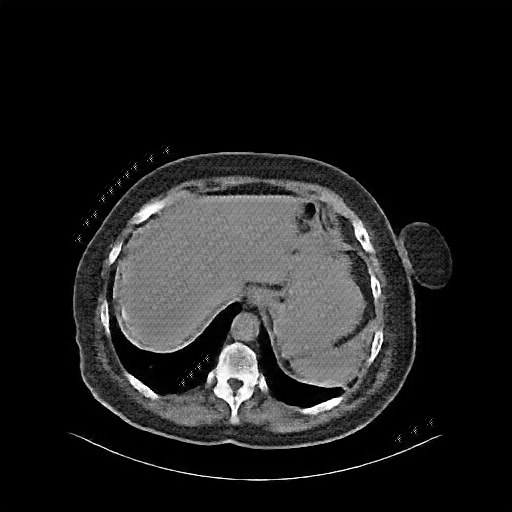

Reconstructed NATIVE CT scan (cycle consistency)

Full window (WL 1023.5, WW 4095 β†’ Low βˆ’1024, High +3071)

Actual HU range: [-620.4, 433.1]

Lung window (WL -600, WW 1500 β†’ Low βˆ’1350, High +150)

Actual HU range: [-620.4, 150.0]

Mediastinum window (WL 40, WW 400 β†’ Low βˆ’160, High +240)

Actual HU range: [-160.0, 240.0]